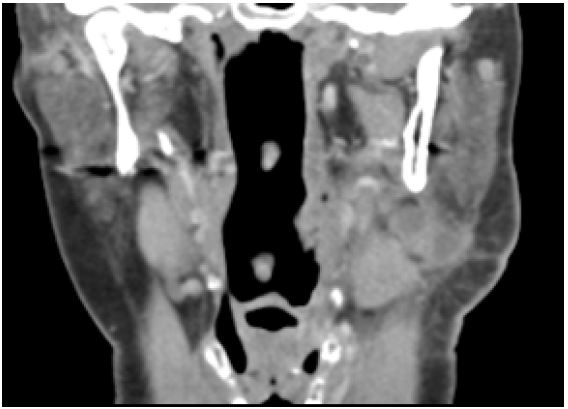

A Computed Tomography-scan (CT-scan) was performed to assess the presence of pus in the fascial spaces of the perimandibular region on March 17, 2022. This scan revealed swollen cervical lymph nodes and a swollen left submandibular gland (Figure 1). In initial antibiotic treatment with amoxicillin and amoxicillin/clavulanic acid, there was no improvement observed. Subsequent drainage and culture revealed the isolation of Streptococcus constellatus, which was susceptible to ciprofloxacin and clindamycin.

Figure 1: Coronal section of the initial CT-scan showing significant soft tissue swelling of the left submandibular region.